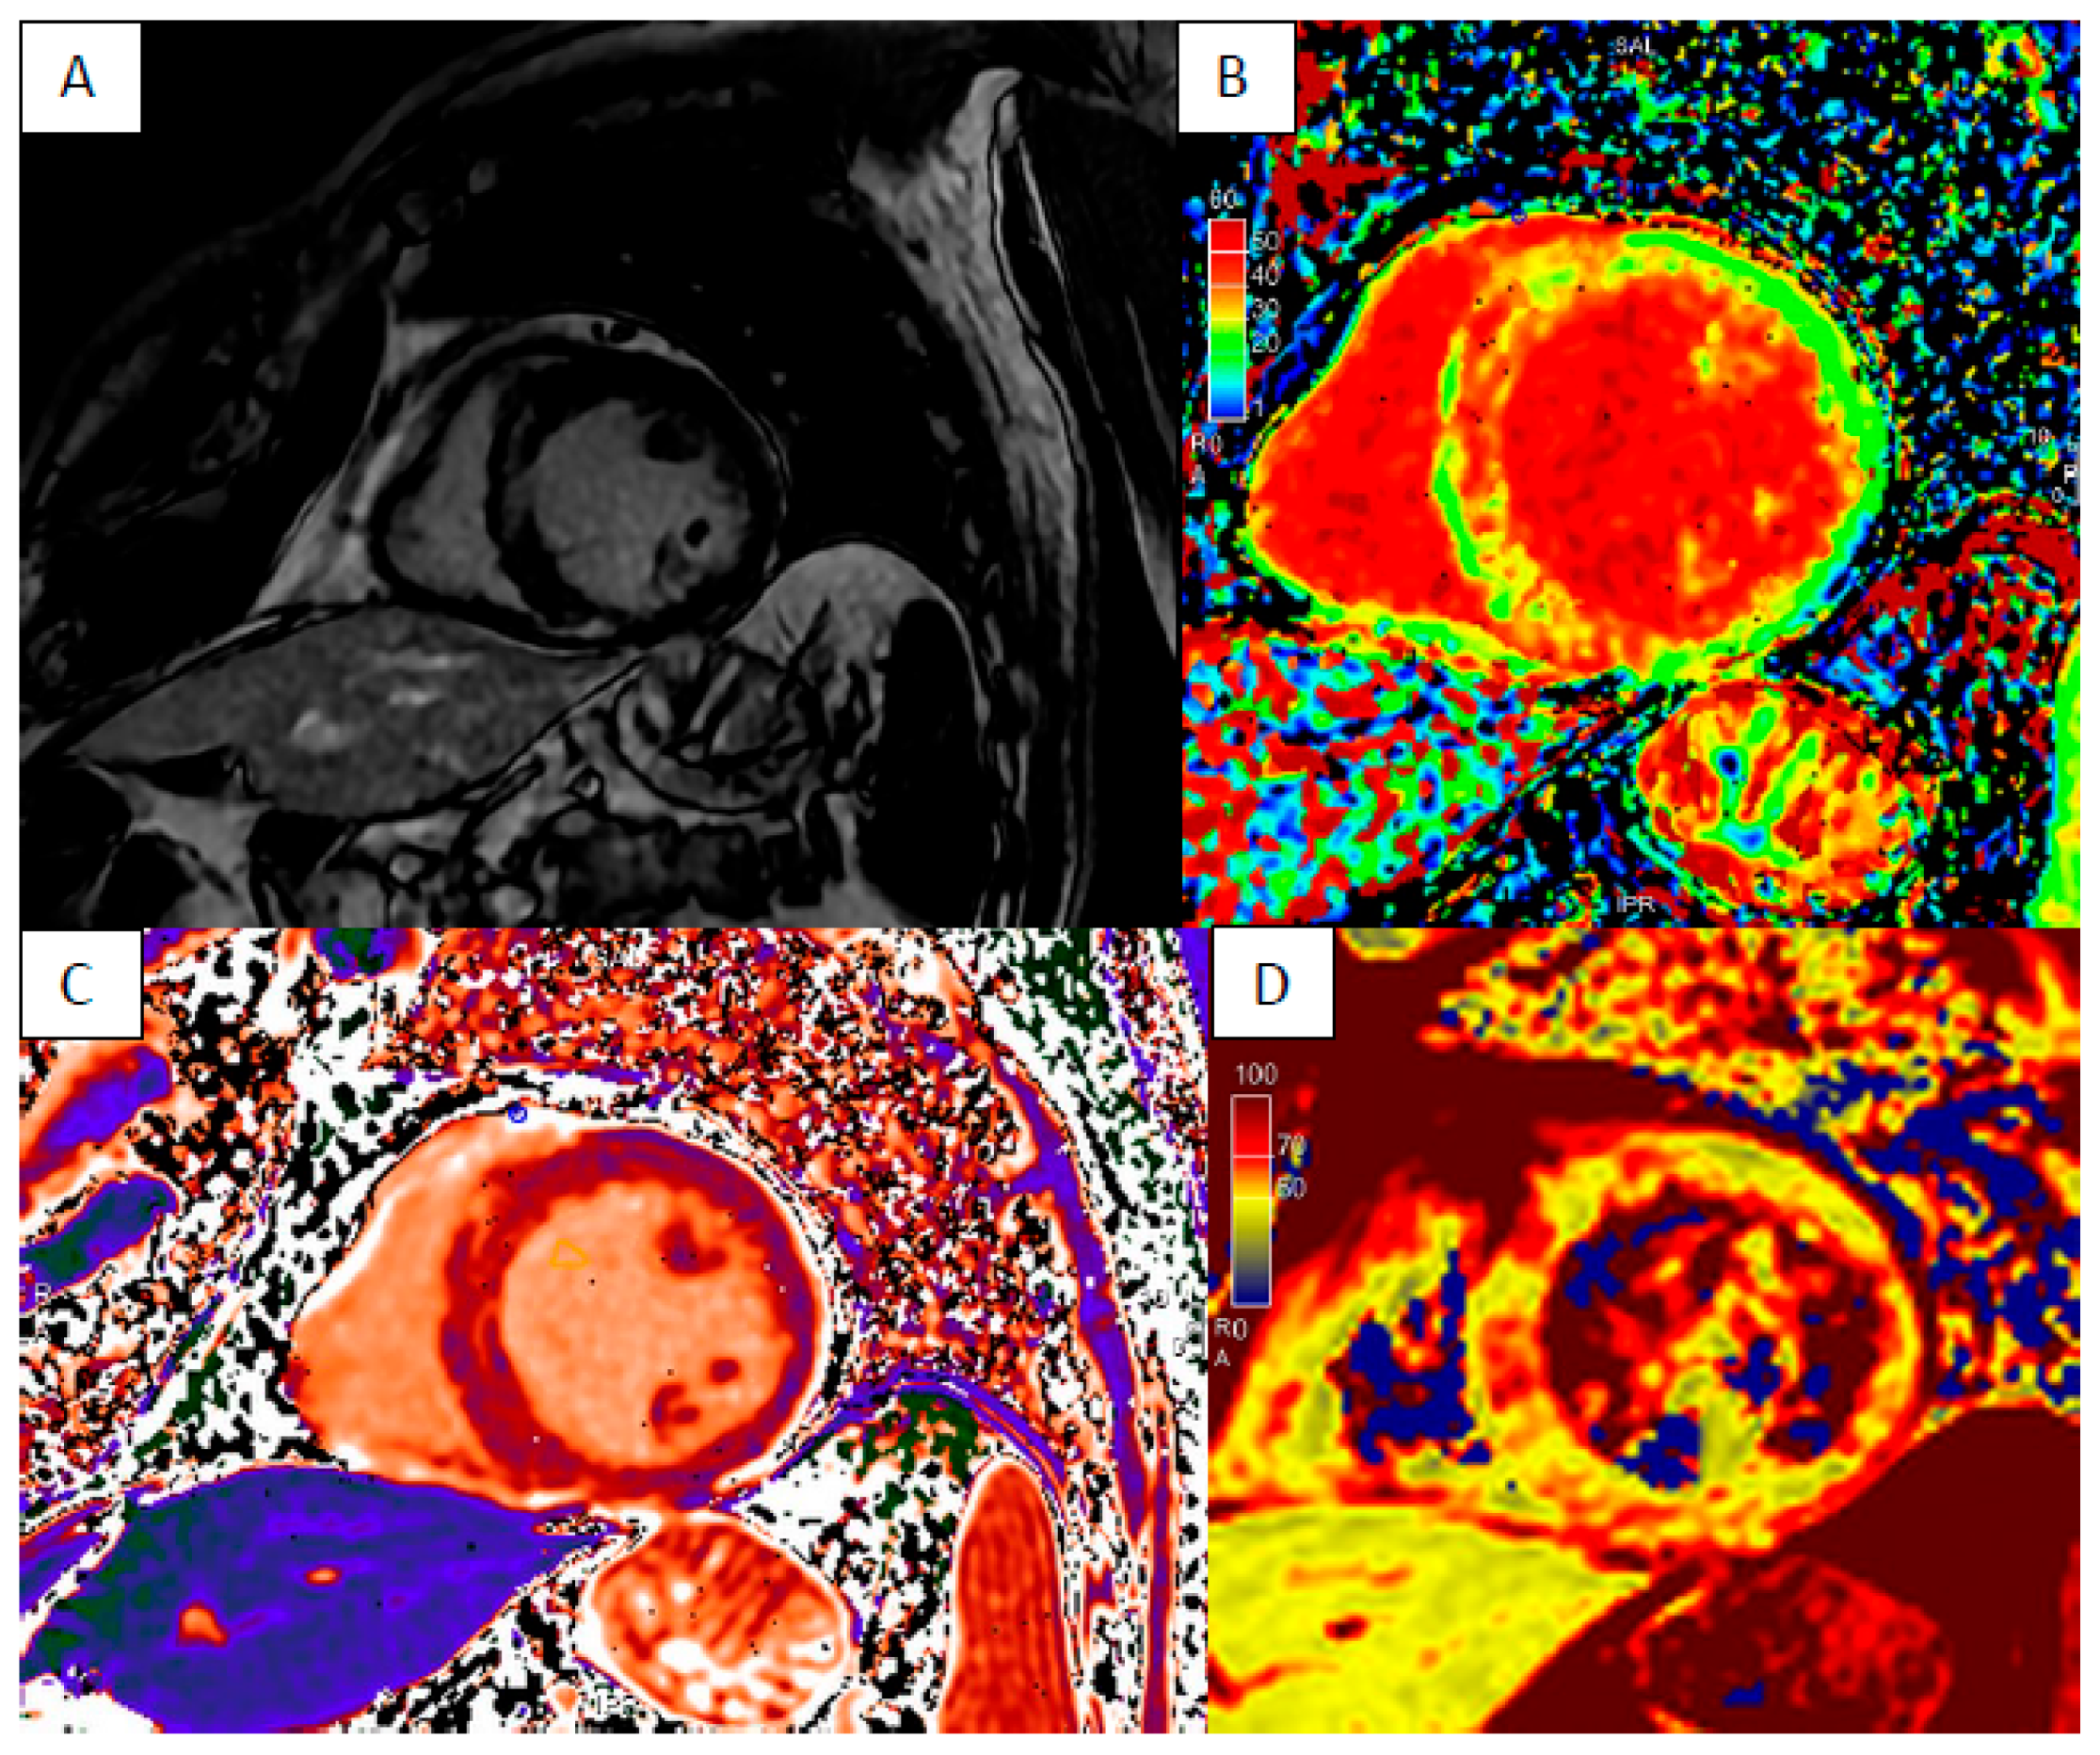

5. Anderson–Fabry Disease